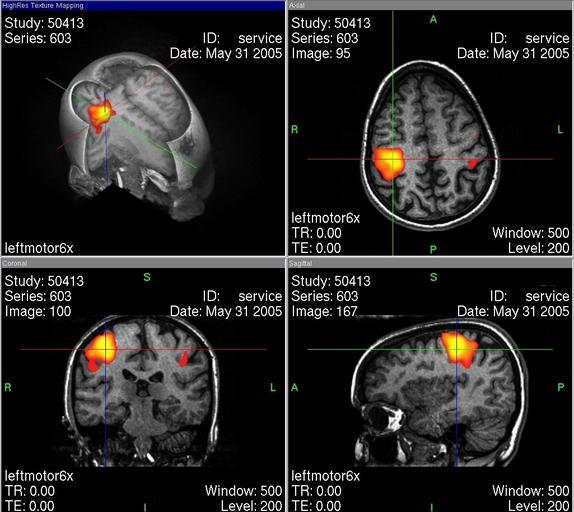

MAKE A MEME View Large Image Fmrtuebersicht.jpg Bildbeschreibung Dieses Bild zeigt eine à bersicht der verschiedenen Betrachtungseben einer fMRT-Aufnahme Quelle Screenshot Fotograf/Zeichner Martin Witte Datum 31 05 2005 de wikipedia 2006-02-10 M R W HH wikipedia de ...

Keywords: Fmrtuebersicht.jpg Bildbeschreibung Dieses Bild zeigt eine à bersicht der verschiedenen Betrachtungseben einer fMRT-Aufnahme Quelle Screenshot Fotograf/Zeichner Martin Witte Datum 31 05 2005 de wikipedia 2006-02-10 M R W HH wikipedia de original upload log page de wikipedia Fmrtuebersicht jpg 2006-02-10 16 29 M R W HH 1025×915×8 164041 bytes <nowiki></nowiki> Magnetic resonance imaging of the brain